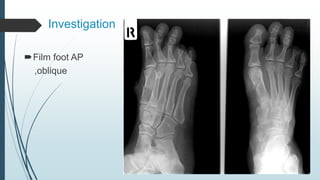

Investigation

Film foot AP

,oblique

Open fracture 1st metasal mid-shaft right foot